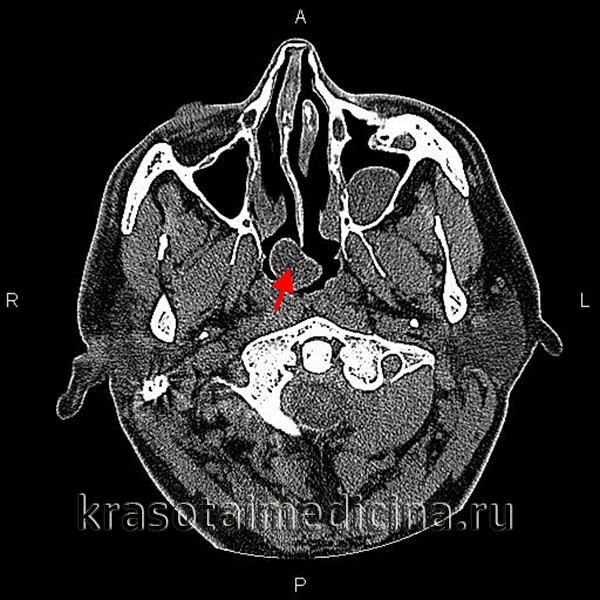

Карман, или сумка Торнвальдта, хорошо виден на рис. 1, 2. Новообразование

расположено в области верхнего констриктора глотки, выстлано слизистой оболочкой с мерцательным эпителием и представляется в виде кистоподобной или, так называемой, корковой формы, когда образовавшаяся в полости засохшая слизь периодически обтурирует одно или несколько выводных отверстий сумки (рис. 3).

Рис. 1. Компьютерная томография. Сумка (карман) Торнвальдта

На компьютерных и магнитно-резонансных томограммах киста Торн-вальдта выглядит как округлое, гиперэ-хогенная структура правильной формы с четкими контурами, не связанная с мышцами глотки. Это позволяет дифференцировать её с другими объемными процессами носоглотки, а именно ретен-ционными и бронхиальными кистами, злокачественными новообразованиями, превертебральными и заглоточными абсцессами, аденоидами.

Данная симптоматика может появиться у больного в любом возрасте, но чаще наблюдается у молодых людей. Учитывая неспецифичность клинических признаков заболевания, его диагностика, как правило, базируется на данных эндоскопического, лучевого и гистологического исследований. В типичных случаях при риноэндоскопии в задневерхнем отделе носоглотки определяется плотное, округлое образование с четкими контурами, содержащее воспалительный экссудат [13]. При рентгенологическом исследовании (компьютерная и магнитно-резонансная томографии) киста выглядит как округлое гиперэхогенное образование правильной формы с четкими контурами, не связанное с мышцами глотки [14, 15].

В типичных случаях при эндориноскопии в задневерхних отделах носоглотки определяется плотное, напряженное, гиперемированное, округлое образование с четкими контурами, содержащее воспалительный экссудат. На компьютерных и магнитно-резонансных томограммах киста Торнвальдта выглядит как округлое, гиперэхогенное образование правильной формы, с четкими контурами, не связанное с мышцами глотки. Это позволяет дифференцировать её с другими объемными процессами носоглотки, в частности, с интрааденоидными, ретенционными кистами, злокачественными новообразованиями носоглотки, превертебральными и заглоточными абсцессами, хоанальным полипом, которые на томографических срезах имеют другую конфигурацию.